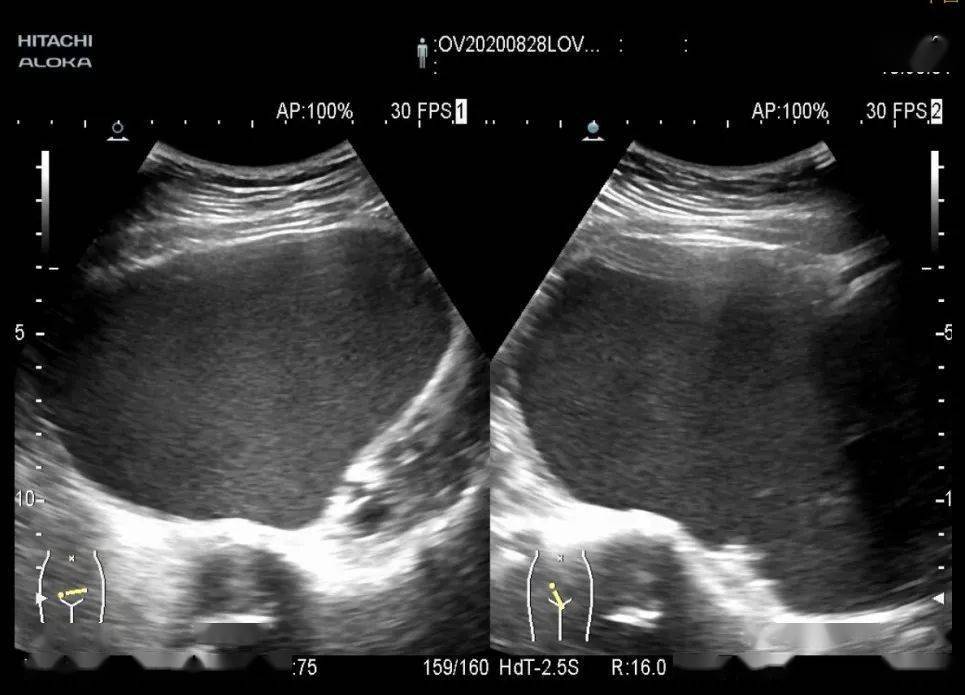

巨大的"巧克力囊肿"? - 超声医学讨论版 - 爱爱医医学论坛

图片尺寸720x540